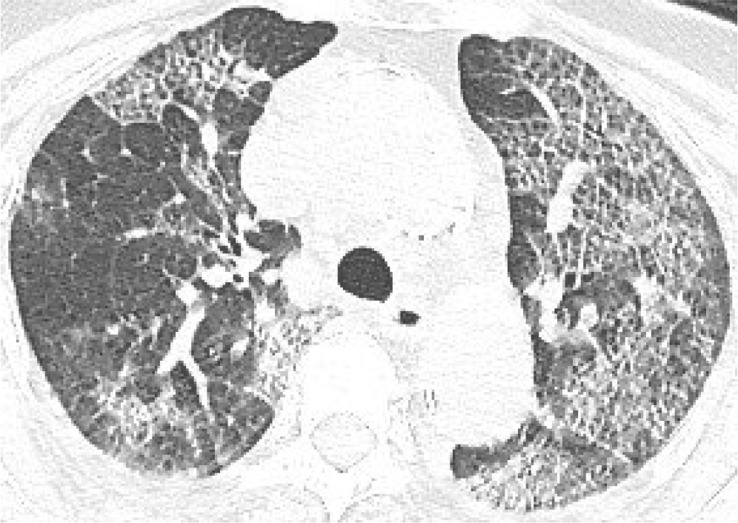

According to the guideline [9], CT examination is strongly recommended as a test for COVID-2019. According to the guidelines, the typical image of COVID-2019 presents multiple patchy ground glass opacity (GGO) along the subpleural and bronchovascular bundles in both lungs, separated by meshed or thickened lobular septa as crazy-paving pattern (54.2%) (Fig. 1, Fig. 2, Fig. 3, Fig. 4 ) and multiple patchy or large patchy consolidation in both lungs (Fig. 5 ), with thickening of interlobular septa, mainly in the middle and lower lobes (31.3%). It is consistent with the findings of Wang's [7] review of 138 cases (the CT findings of all cases involved both lungs), Huang's [1] review of 41 cases (all cases involved both lungs) and Song's [8] review of 51 cases (distribution: the lesions involved both lungs in 86% of patients, the lower lobe in 90% of patients, and the peripheral lung field in 86% of patients; density: 39% of the total number of lesions showed as GGO with reticular and/or interlobular septal thickening). Atypical images showed single lesion [10] (Fig. 6 ) and single or multiple consolidation nodules in the center of lobules, surrounded by ground glass opacities [9]. Both Song [8] and Pan [11] found that COVID-19 rarely caused mediastinal lymphadenopathy or pleural effusion.

Fig. 3.

83-year old female with intermittent fever (maximum temperature of 38.8 °C) for 1 week. Nucleic acid test: positive. Imaging examination: CT showed diffuse patchy GGO with crazy-paving pattern in both lungs.

Fig. 4.

67-year old female with cough and sputum for half a month. Nucleic acid test: positive. Imaging examination: CT showed diffuse patchy GGO and consolidation with crazy-paving pattern in both lungs.